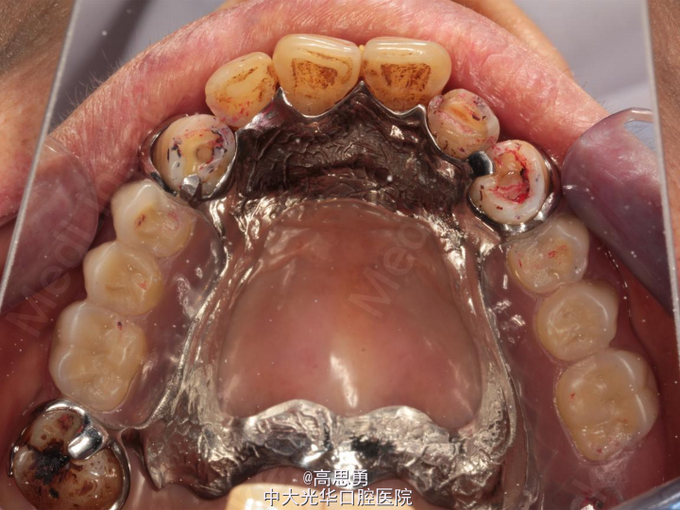

诊断: 1、牙列缺损(上颌肯氏II类I分类,下颌肯氏II类II分类) 2、#13慢性根尖周炎 3、#11、#12、#13、#21、#22、#23、#33、#42、#43、#44楔状缺损 4、慢性牙周炎 治疗计划 1、#13转牙体牙髓科做RCT 2、转牙体牙髓科对#11、#12、#13、#21、#22、#23、#33、#42、#43、#44楔状缺损 充填治疗 3、转牙周科进行牙周洁治 4、择期RPD修复 备选修复方案: 1、#13RCT后截冠后,上下颌覆盖义齿修复; 2、#13RCT后冠修复,上下颌可摘局部义齿修复; 3、#13RCT后树脂充填,上下颌可摘局部义齿修复; 4、#13拔除后,上下颌可摘局部义齿修复。 患者意愿:患者希望尽量保持#13的天然形态,要求费用尽量低,但能恢复正常咀嚼功能。 最终治疗方案:根据患者的年龄、身体状况、治疗周期、经济状况,患者最终选择方案5,即#13RCT后树脂充填,上颌结合卡环式可摘局部义齿修复;下颌可摘铸造支架式局部义齿修复。 治疗过程: 1、临床检查和#13树脂充填 对患者进行全面的口腔检查,用Z350树脂充填#13,调HE,抛光。 2、研究模型 调拌藻酸盐印模材料于2号成品托盘上取上下颌研究模,灌注石膏模型,研究分析、制定治疗计划,并制作个别托盘。 3、基牙预备 对#13近中、#23远中、#27近中、#34近中、#47近中常规制备支托凹,抛光。 4、工作模型 调拌藻酸盐印模材料于个别托盘上。做一定的边缘整塑,取上下颌研究模,灌注石膏模型。 5、试戴支架 检查支架的就位、固位可,无翘动,调HE,抛光,用蜡堤取颌位关系,上颌架,排牙,比色C4。 6、试排牙 检查义齿的就位、固位可,无翘动,观察人工牙的咬合状况,尖窝接触良好,正中颌位能重复,患者无诉不适,面容自然,外观满意。送加工厂充胶制作最终修复体。 7、试戴 检查义齿的就位、固位可,无翘动,咬合关系正确,利用咬合纸检查,上下颌尖窝接触均匀全面,抛光,患者表示满意,嘱注意事项,定期复诊。

游离端缺失修复后的不稳定现象的处理 不稳定是指义齿在行使功能中出现明显的翘起、下沉、摆动、旋转等现象。其原因是存在支点或转动轴和义齿存在游离端。其类型有平动性不稳定和转动性不稳定,平动性不稳定是由基托下组织的可让性引起的, 只要有合理的咬合设计、较大的基托面积支持及无明显的支点存在等, 此平动性不稳定就可视为均匀下沉的不稳定, 若牙合力作用能维持在基托下组织所能承受的生理限度就之内,这样的义齿可视为合理的稳定的。肯氏I、II类的牙列缺损的修复正是由于存在义齿游离端而容易出现转动性不稳定,而转动性不稳定由于杠杆作用而使作用于基牙、基托下组织的牙合力被放大,或作用力的方向被改变,从而造成对基牙、基托下组织严重伤害, 故其是义齿设计中重点克服的问题。对于游离端可摘义齿, 一般采用混合支持式或粘膜支持式的设计。如:肯氏I、II类多牙列的后牙缺失并伴有余留牙松动时,应该消除一切支点,采用粘膜支持式的义齿为宜。而肯氏类个别或少数后牙缺失且余留牙情况较好时,可在基牙近缺隙侧设计近中支托,且结合采用应力中断卡环、连接体缓冲等, 并充分利用平衡法和对抗法,采用混合支持式的义齿为宜。有学者建议,远中游离端缺失的患者,戴用可摘局部义齿一段时期后应作复查,游离端基托下沉、翘动,及时垫底消除基牙过负荷的因素。故采用合理的稳定设计,患者又注意保持口腔清洁卫生, 以及出现问题后及时修改和调整, 从而保证了牙合力分配的良好状态, 则有利于延长义齿的使用年限。